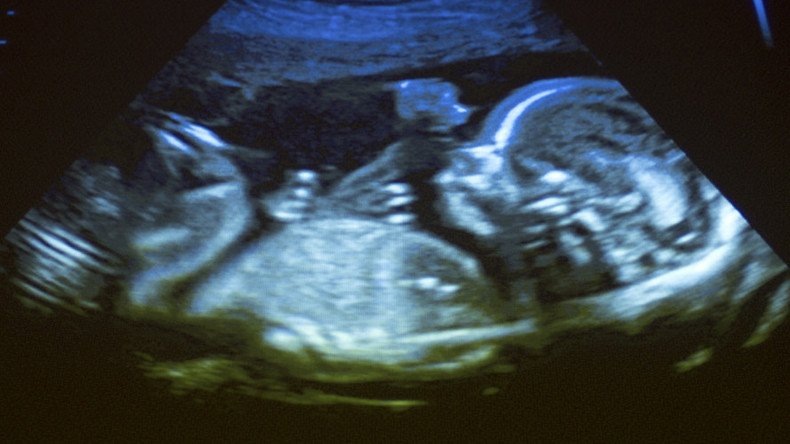

Puerto Rico’s governor signs bill that amends a law to recognize a fetus as a human being